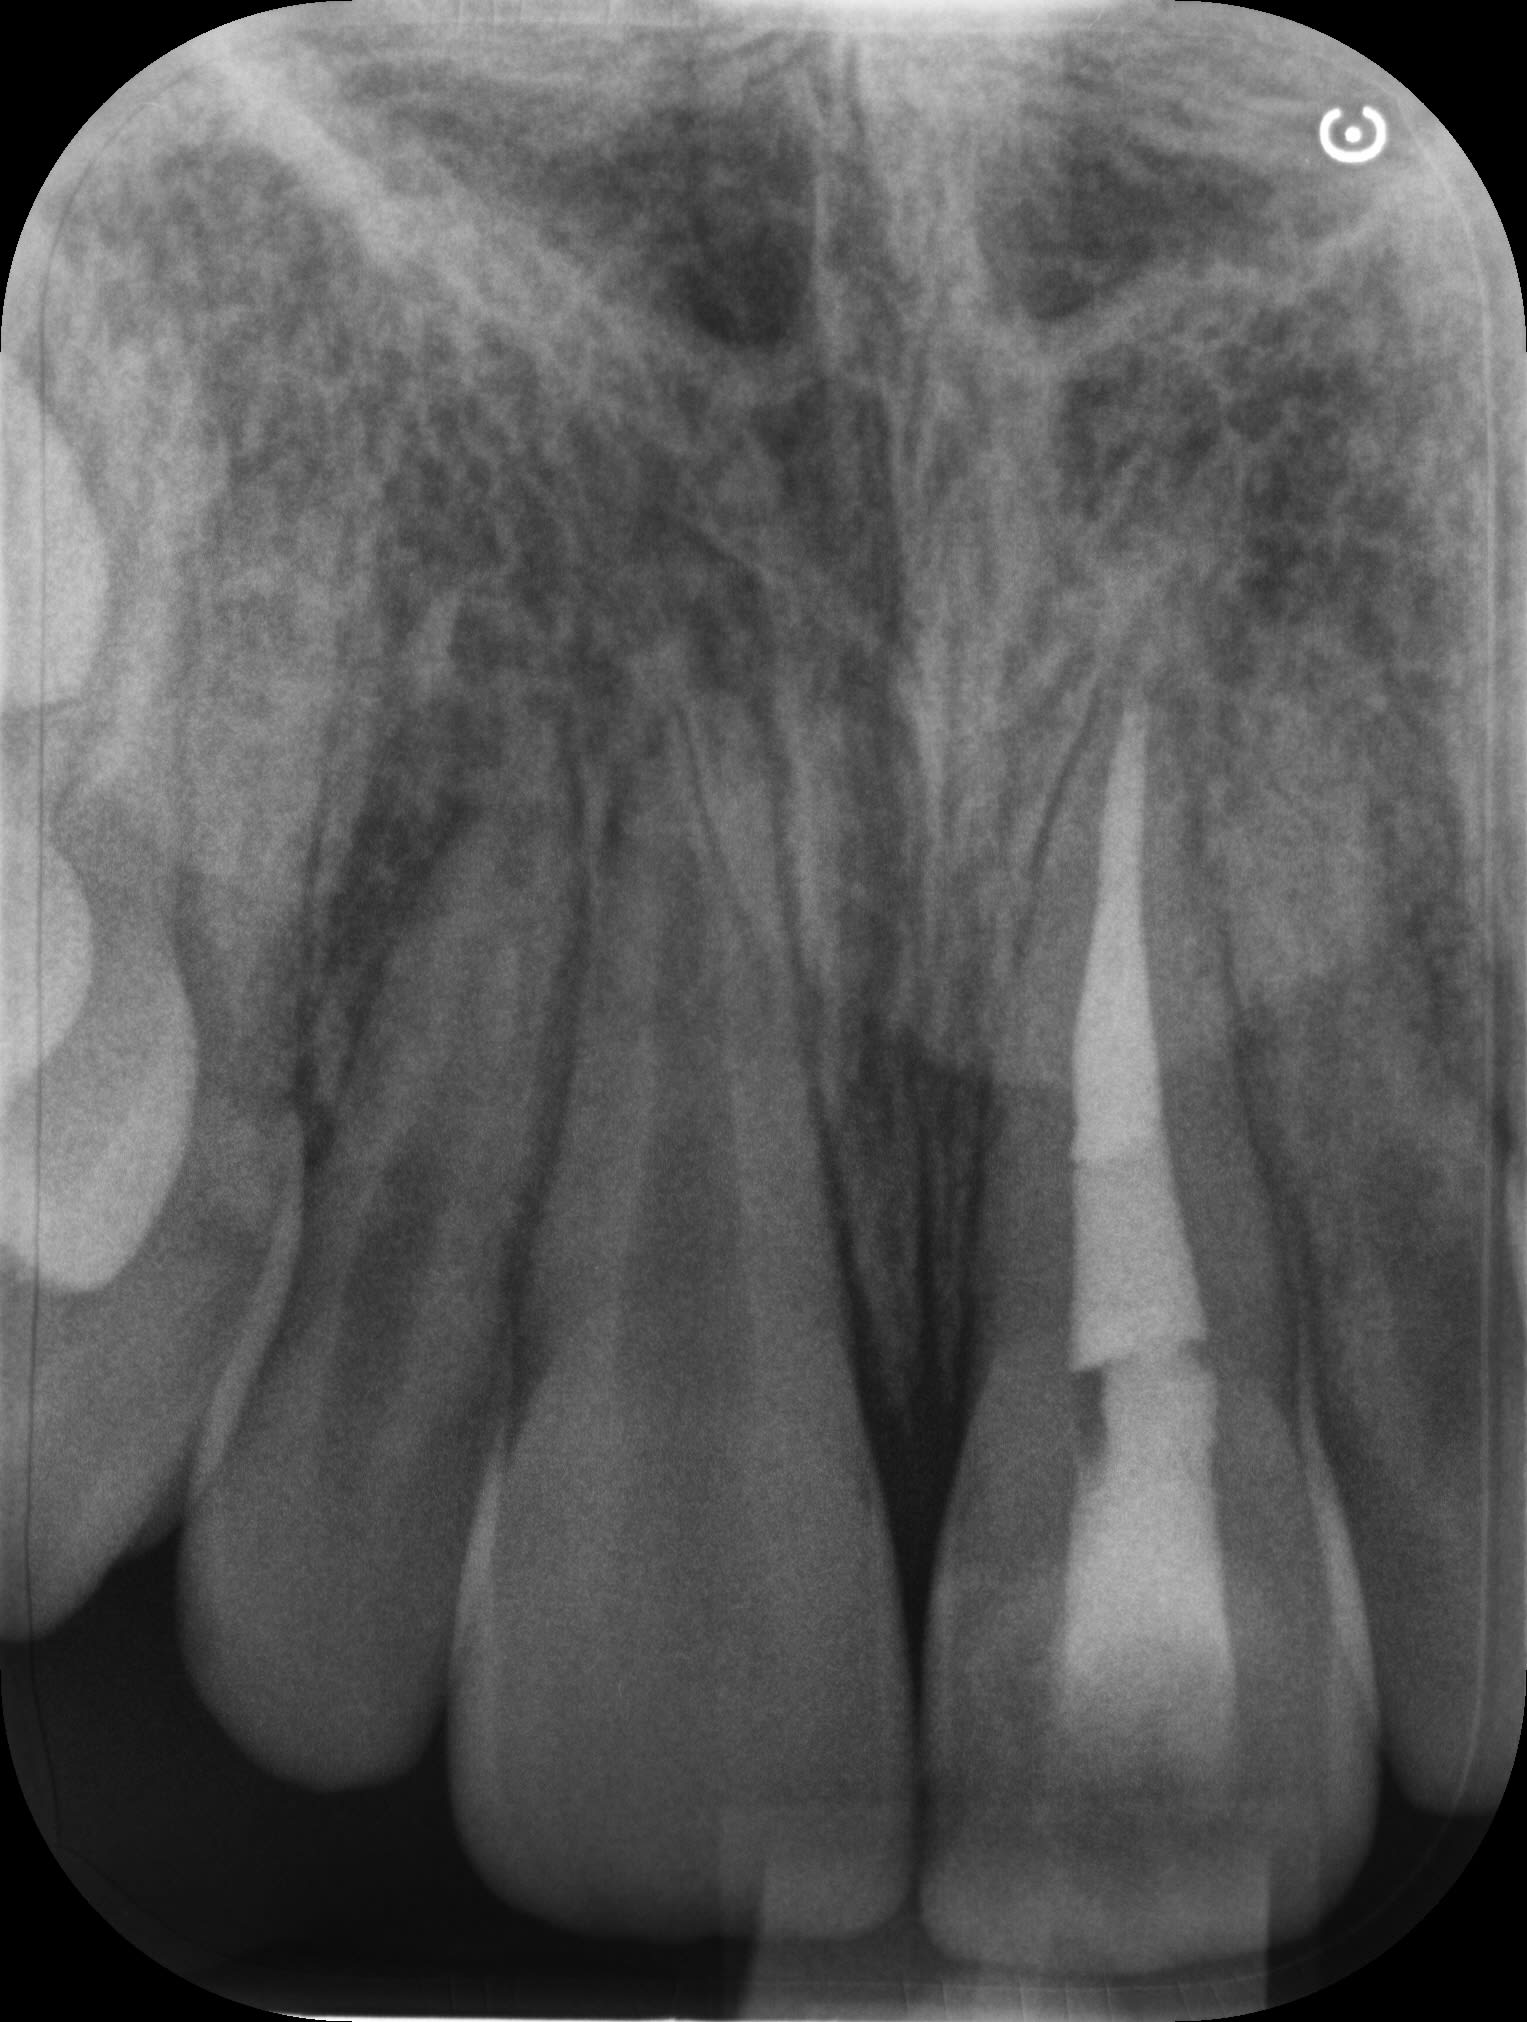

- début du traitement radiculaire sur 21 (pas réalisé par moi)

- NB : 2 inter-séances à l'hydroxyde de calcium ont été nécessaire avant l'obturation 30 jours plus tard